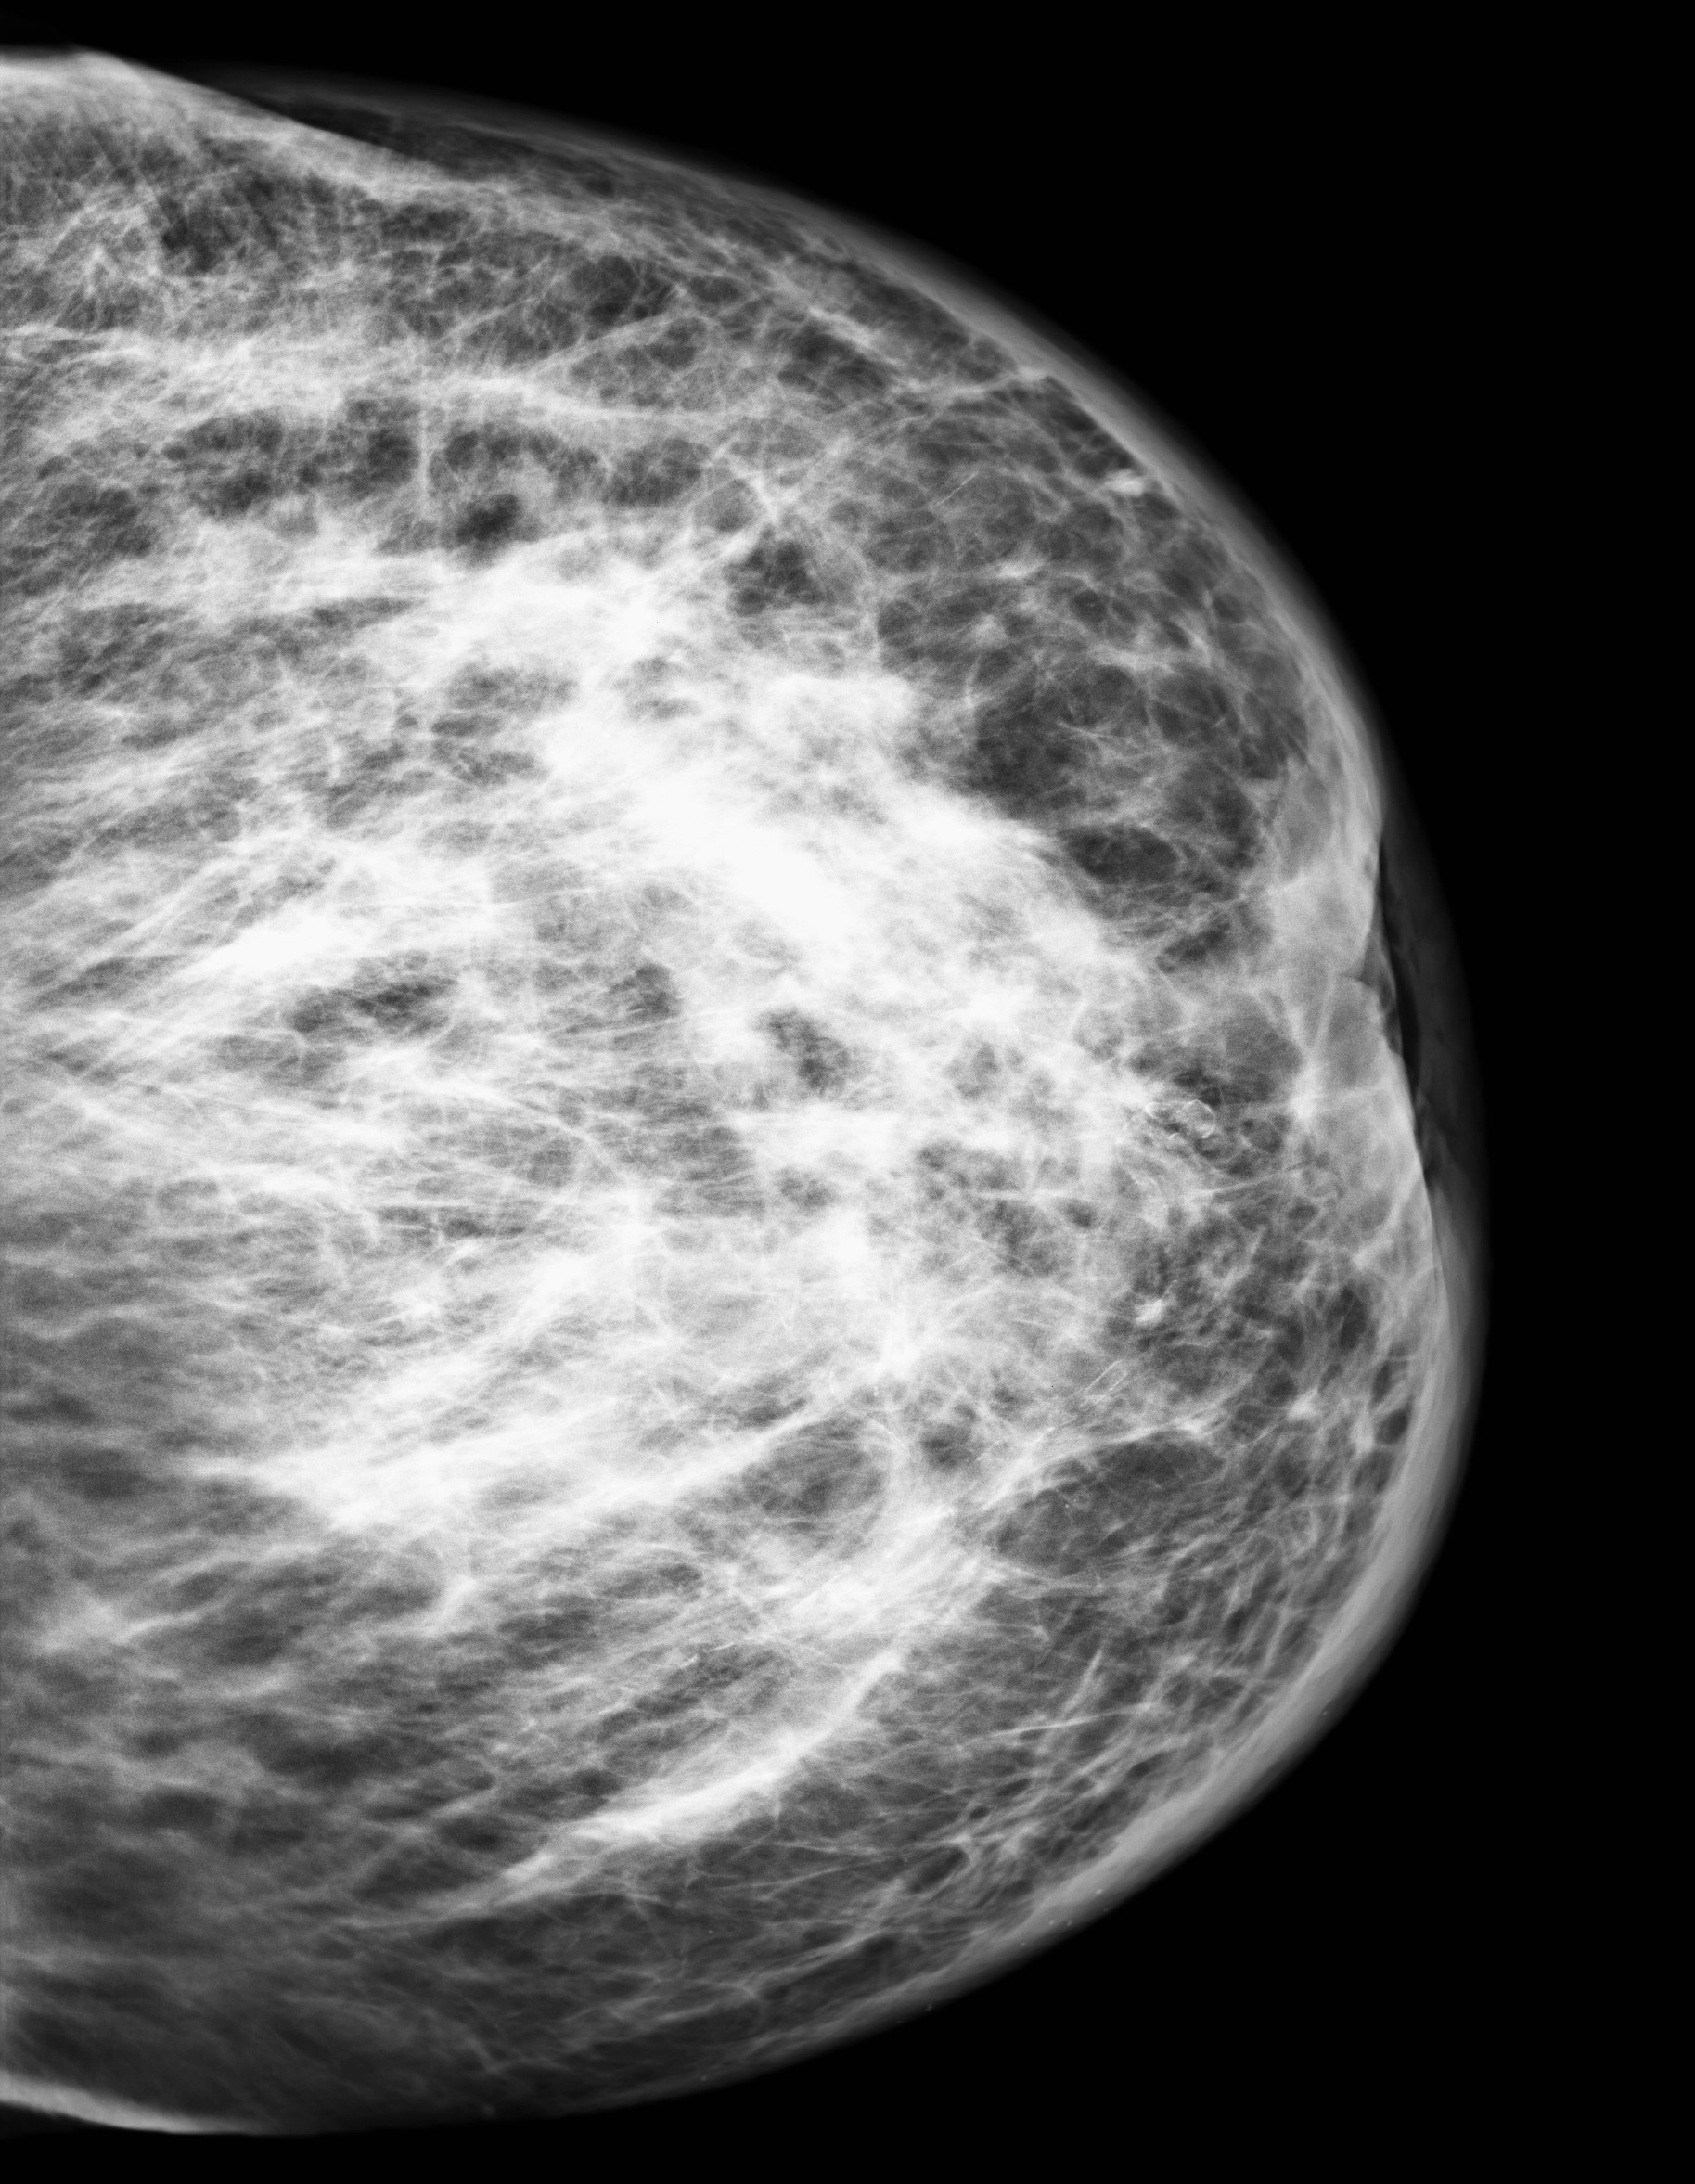

Ung thư biểu mô tiểu thùy vú (Lobular breast carcinoma)